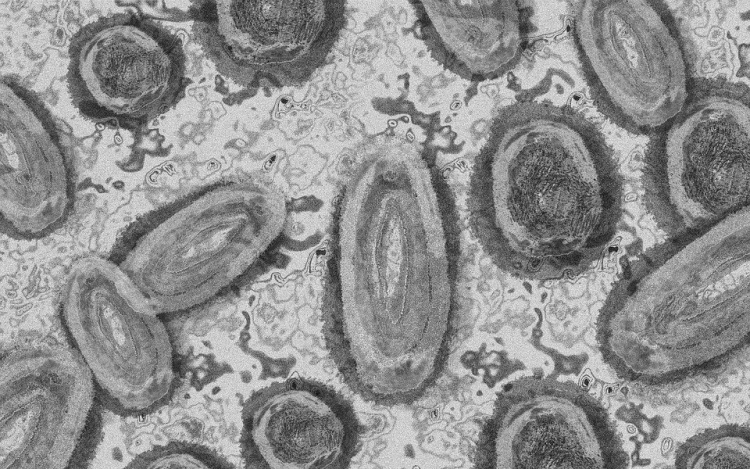

Tovább nőtt a majomhimlő-fertőzöttek száma Magyarországon

Újabb kilenc, 23-50 éves férfinél igazolták a majomhimlő-fertőzést Magyarországon, ezzel 42-re nőtt a fertőzöttek száma - közölte a Nemzeti Népegészségügyi Központ (NNK) csütörtökön az MTI-vel.

A betegség általános, nem specifikus tünetekkel - lázzal, hidegrázással, izomfájdalommal, hátfájdalommal, fejfájással, fáradtsággal), illetve a nyirokcsomók duzzanatával kezdődik, majd 1-3 nappal a bevezető tünetek után bőrkiütések jelennek meg. A kiütések sok esetben először az arcon, majd a tenyéren és a talpon fordulnak elő, de megjelenhetnek a szájnyálkahártyán, a nemi szerveken és a végbél környékén is - olvasható a közleményben.